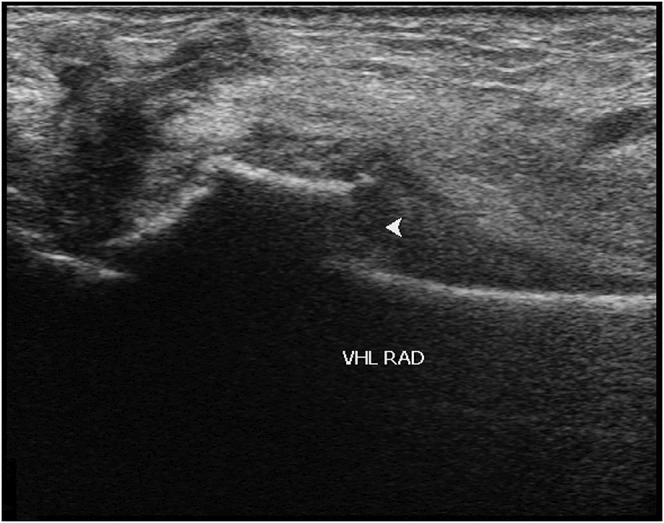

This prospective comparative study involved 91 patients (age, ≥18 years) who had been referred by general practitioners for a conventional radiographic examination of a suspected extremity fracture. No additional clinical examination was performed. Ultrasound examination was consistently carried out prior to conventional radiographic examination, which was regarded as the gold standard. At the end of the study, the positive scans were confirmed by a specialist who was highly skilled in ultrasonography.

The prevalence of fractures in the study population was 27%. Ultrasonography had a sensitivity of 92%, a specificity of 94%, a positive predictive value of 85%, a negative predictive value of 97%, a positive likelihood ratio of 15.33, and a negative likelihood ratio of 0.085. There seemed to be no association between the anomalous results and patient age or the specific anatomical region of the fracture.

The present study indicates that ultrasonography, when performed and interpreted by experienced ultrasonographers, has high accuracy for the diagnosis of a suspected extremity fracture. No systematic differences were found between the results of radiography and ultrasonography, and ultrasonography showed a high sensitivity and specificity.